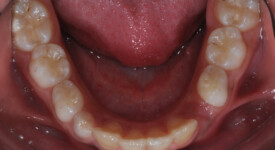

This is an example of a teenage patient with photographs of their smile before and after treatment at Braceline. Our orthodontic treatments are designed to provide maximum results in minimal time and to help you achieve the smile you always wanted!

Before Transformation!

After Transformation!